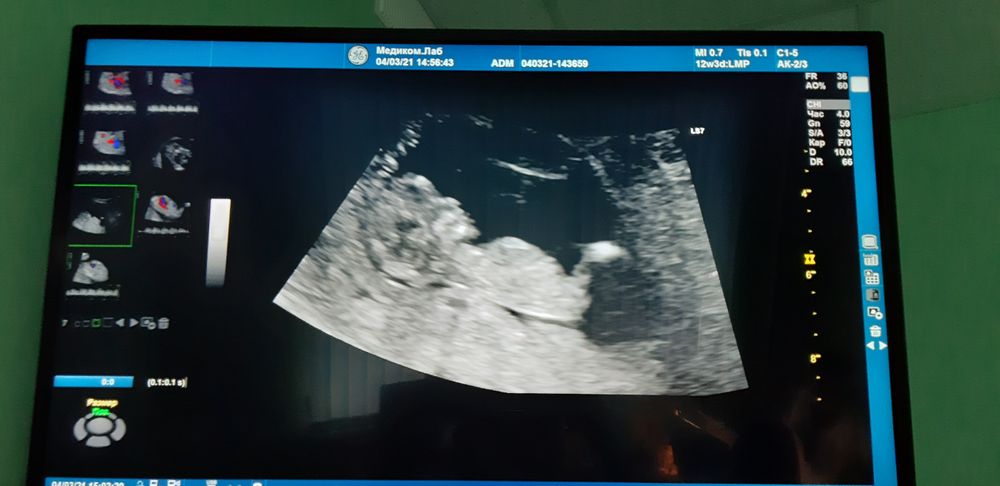

Новогодние праздники, муж знает о задержке, просит сделать тест, отправляет в ванную, а я сопротивляюсь, говорю ну подумаешь 3 дня задержки,бывает сбой,а он настаивает и просит сделать, уговорил, пошла в ванную, делаю все медленно не торопясь , боясь увидеть отрицательный тест... и тут на моих глазах появляется первая, а затем вторая полоска... она слабая очень , но видна на глаз. Выбегаю с ванны, говорю мужу ты станешь папой! Руки дрожат, на глазах наворачиваются слезы от счастья, он улыбается с широкими выпученными глазами и спрашивает в недоумении: ЧТО??? ЧТО??? Покажи !!!??? Положительный??? Счастливый радуется, улыбается обнимает меня))) Так мы и узнали,что во мне зародилась новая жизнь. Мы мечтали об этом, мы загадали на Новый 2021ый Год малыша и вот Всевышний подарил нам его, наше чудо. Нашего УЛЫМКУ! Это безмерное счастье. Беременность протекает хорошо, сегодня нам уже 18 недель, время летит, животик растет и уже чувствую его нежные маленькие пиночки, толчки. БЛАГОДАРЮ ВСЕЛЕННУЮ, ВСЕВЫШНЕГО, БЛАГОДАРЮ ЗА ВОЗМОЖНОСТЬ СНОВА СТАТЬ МАМОЙ И ПОДАРИТЬ ЭТОМУ МИРУ ЕЩЕ ОДНУ ЖИЗНЬ, ЕЩЕ ОДНОГО УНИКАЛЬНОГО ЧЕЛОВЕКА, УНИКАЛЬНОГО МУЖЧИНУ! Верьте , мечтайте, загадывайте, ведь МЕЧТЫ СБЫВАЮТСЯ!!!